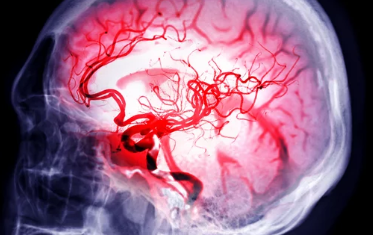

갑작스러운 두통, 어지럼증, 한쪽 팔다리 마비... 이러한 증상들은 뇌졸중의 전조 증상일 수 있습니다. 뇌졸중은 뇌혈관이 막히거나 터져서 발생하는 질환으로, 빠른 진단과 치료가 매우 중요합니다. 하지만 많은 사람들이 뇌졸중 전조 증상을 가볍게 여기거나 다른 질환과 혼동하여 치료 시기를 놓치는 경우가 많습니다. 오늘은 뇌졸중 전조 증상을 자세히 알아보고, 응급 상황 발생 시 대처 방법과 예방법까지 꼼꼼하게 살펴보겠습니다.